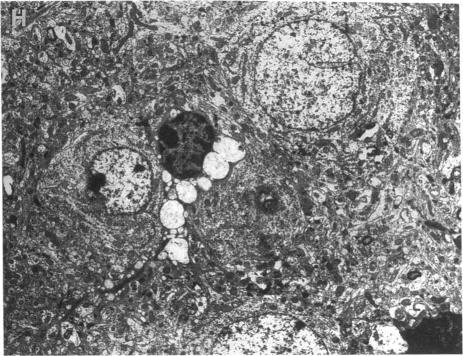

Recombinant mouse beta-glucuronidase administered intravenously to newborn mice with mucopolysaccharidosis type VII (MPS VII) is rapidly cleared from the circulation and localized in many tissues. Here we determine the tissue distribution of injected enzyme and describe its effects on the histopathology in 6-wk-old MPS VII mice that received either one injection of 28,000 U recombinant beta-glucuronidase at 5 wk of age or received six injections of 28,000 U given at weekly intervals beginning at birth. These mice were compared with untreated 6-wk-old MPS VII mice. The single injection decreased lysosomal distention in the fixed tissue macrophage system. MPS VII mice that received multiple injections had 27.8, 3.5, and 3.3% of normal levels of beta-glucuronidase in liver, spleen, and kidney, respectively. Brain had detectable beta-glucuronidase, ranging from 2.0-12.1% of normal. Secondary elevations of alpha-galactosidase and beta-hexosaminidase in brain, spleen, liver, and kidney were decreased compared with untreated MPS VII mice. Although no improvement was observed in chondrocytes, glia, and some neurons, the skeleton had less clinical and pathological evidence of disease and the brain had reduced lysosomal storage in meninges and selected neuronal groups. These data show that recombinant beta-glucuronidase treatment begun in newborn MPS VII mice provides enzyme to most tissues and significantly reduces or prevents the accumulation of lysosomal storage during the first 6 wk of life. Whether therapy begun later in life can achieve this level of correction remains to be established.